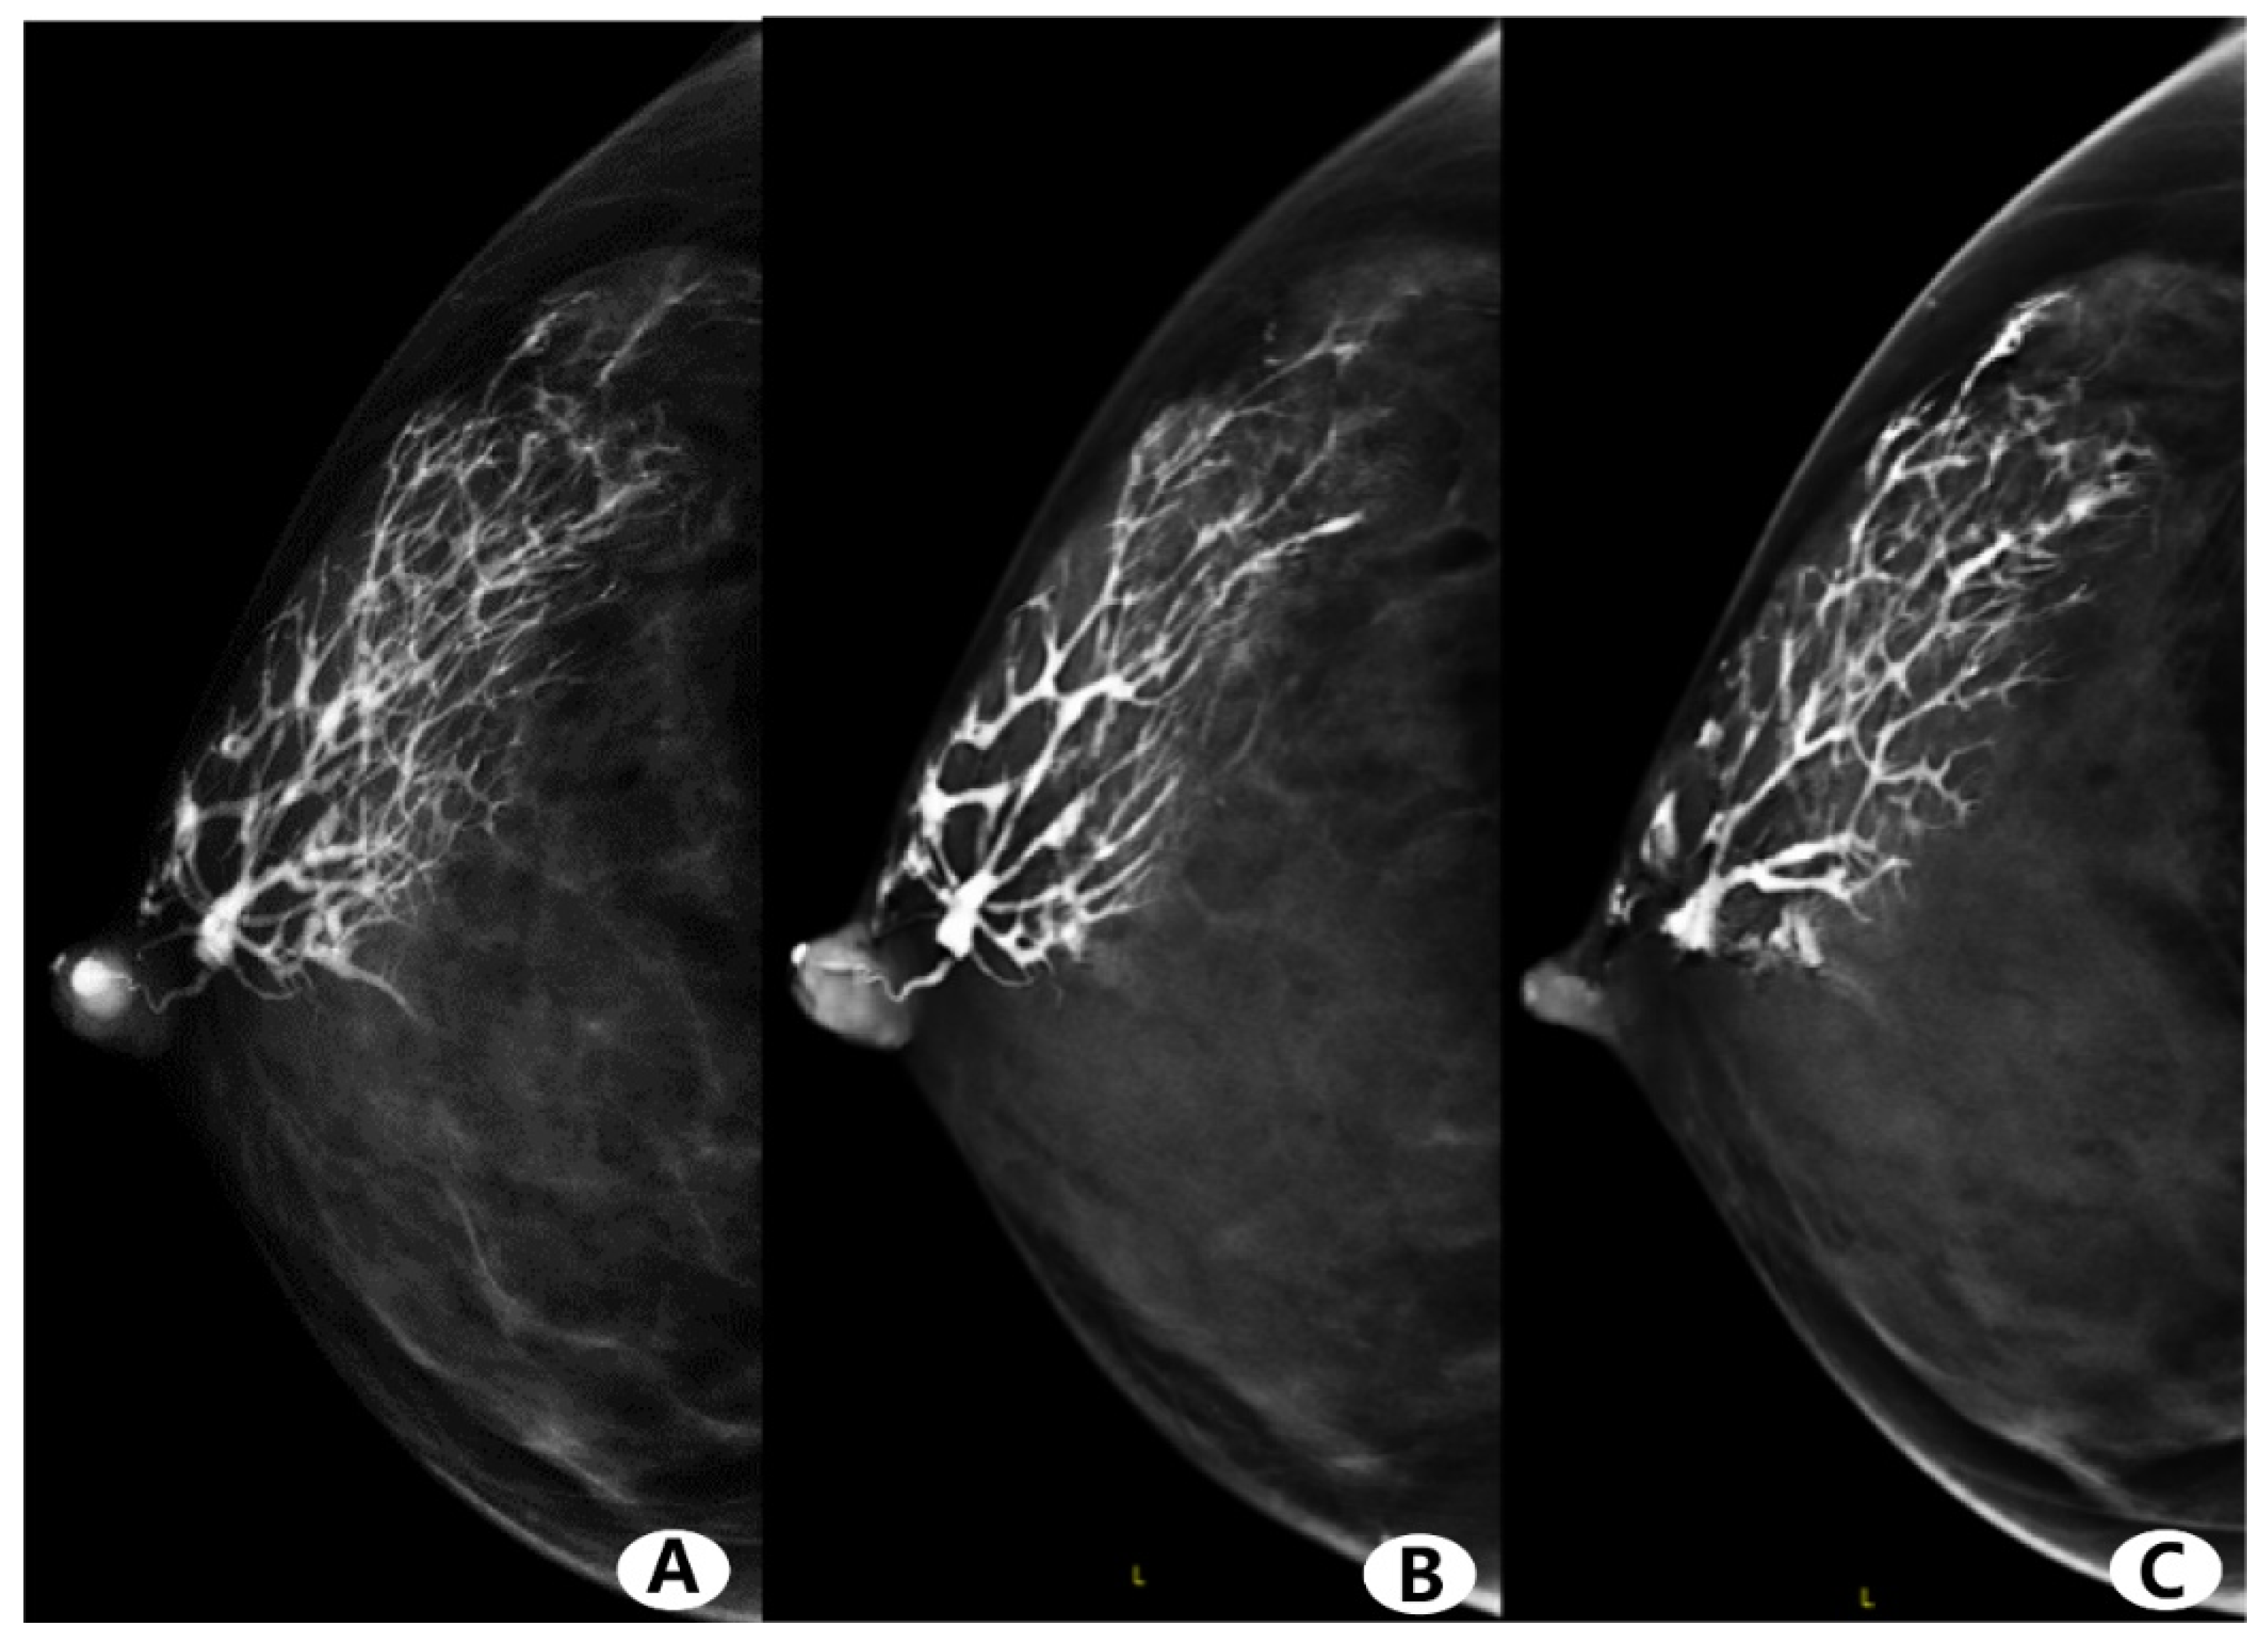

3.4. Imaging Finding